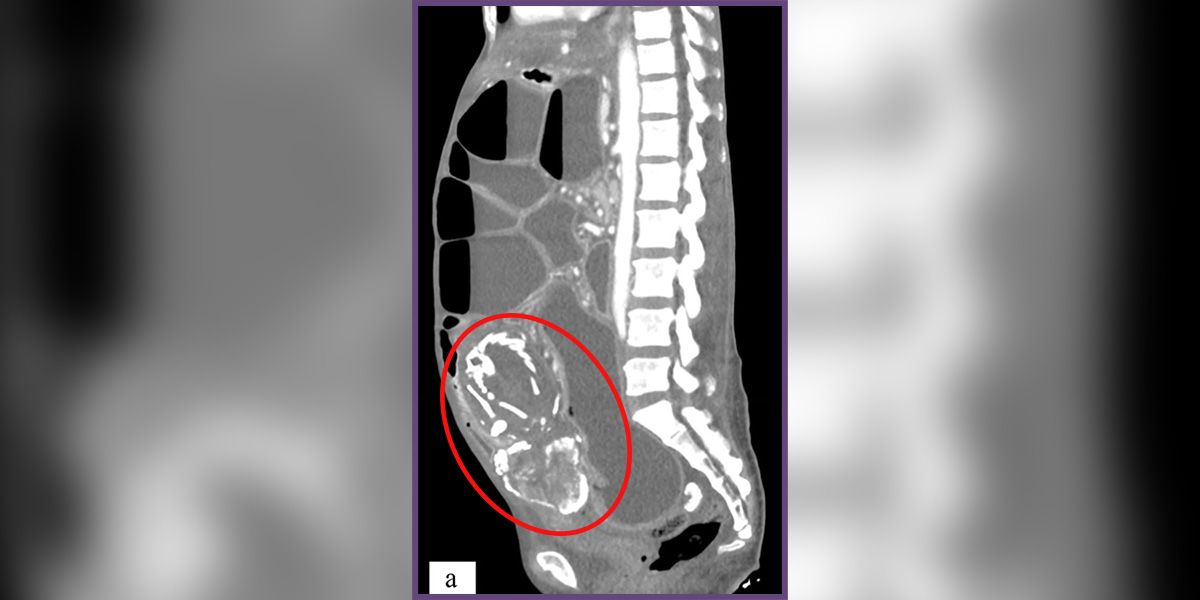

Der Scan (Bild) zeigt den knöchernen Fötus in der Bauchhöhle der Frau.